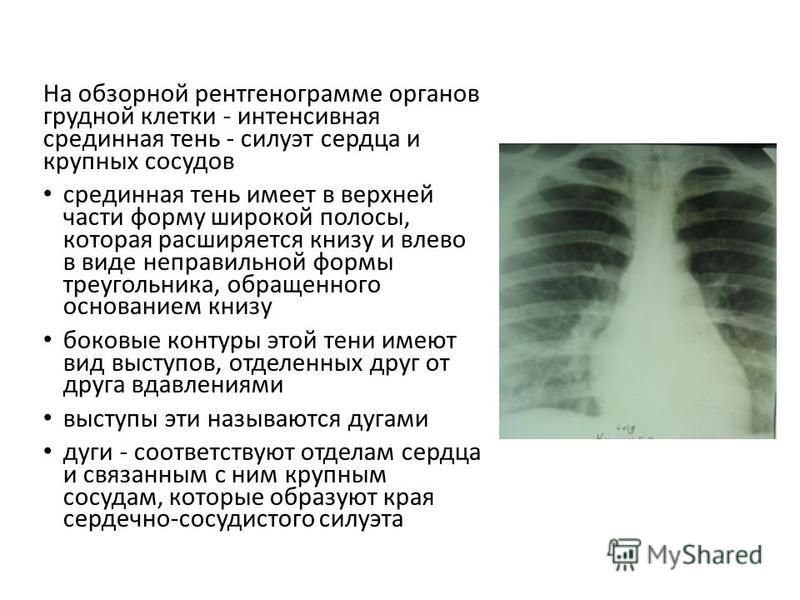

Что такое малоконтрастная рентгенограмма органов грудной клетки